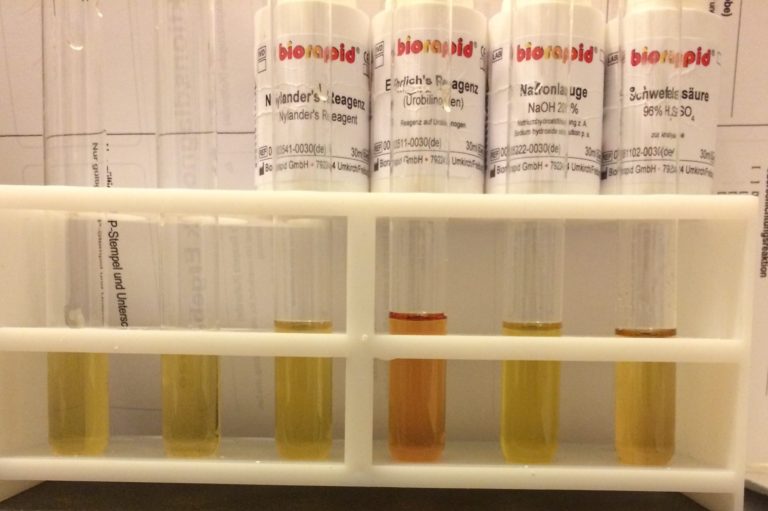

klassische Harndiagnostik

- Traditionelle Harndiagnostik,

- mikroskopische Untersuchungen von Abklatschpräperaten zum Ausschluss parasitäre Krankheiten.

- Blutentnahmen, Stuhldiagnostik und Stoffwechselprofile Versendung in modernster Labore (externes Labor IMD Berlin)